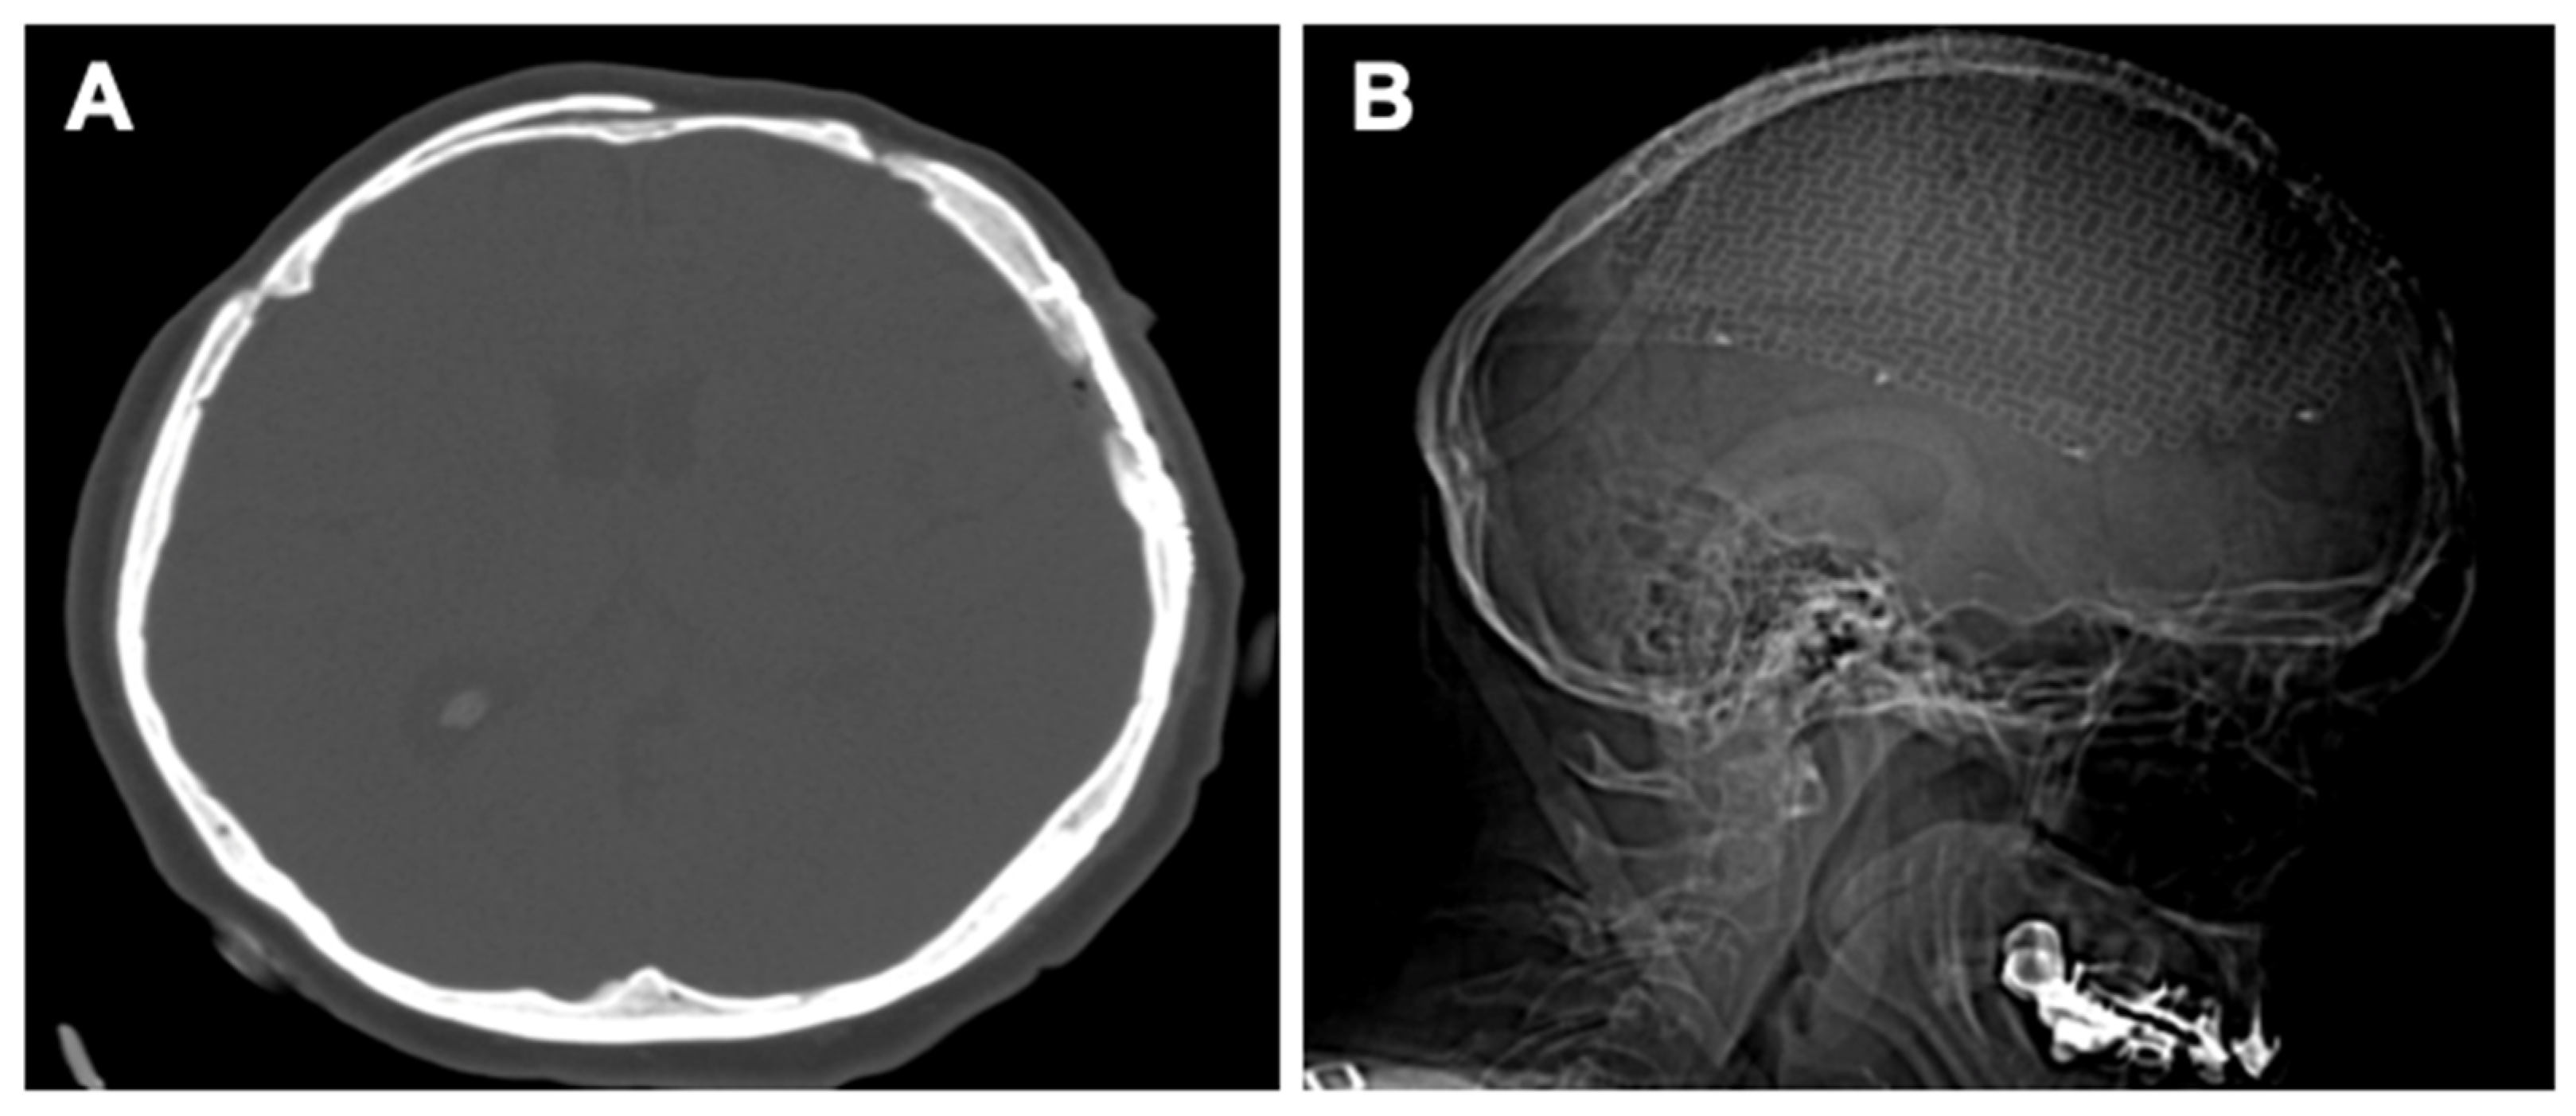

| Current study | 50/F | Frontal bone and left parietal bone | Frontal and parietal headache, nausea, and vomiting | Symptoms increasing in intensity from a month before | CT and MRI: two hypodense lesions (7 cm and 8 cm) with multiple interior calcifications and compressive effect on the cerebral parenchyma | En-bloc resection in two stages: 1. Frontal craniotomy and reconstruction with intact external plate; 2. Left parietal craniotomy with titanium and PMMA cranioplasty |